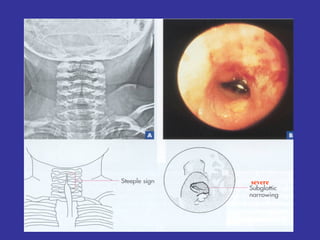

LARYNGITIS-LARYNGOTRACHEOBRONCHITIS-VIRAL CROUP Viral infection characterized by:  Barking cough, Inspiratory stridor, Hoarseness, due to subglottic  inflammation Etiology:  Parainfluenza virus type 1(m.c), type 2 and 3, RSV, influenza A/B Pathophysiology:  -Virus enters  body via respiratory droplets through nasopharynx airway -There is an immune response, resulting in subglottic narrowing  -Edema and erythema of the mucosa of the subglottic tissue and / or  tracheal mucosa,  further narrowing  the airway, resulting in stridor, hoarseness, cough    may lead to those  complications:  Ventilation/perfusion mismatch Hypoxia/hypercarbia: Air hunger, Anxiety/Lethargy

Epidemiology:  Occurs mainly between 6-36 months.  Self limited Ds. lasting 3-5 days. Prevalent in late fall/winter Person-to-person transmission via respiratory droplets. S/S:  Prodrome:  Coryza, nasal congestion, sore throat, cough, low grade fever   Characteristic:  hoarse voice and barking cough (mainly at night),  loud inspiratory stridor,  mild respiratory distress (sternal / suprasternal retractions, cyanosis)  no sign of toxicity.  LAB:  X-Ray:  The AP x-ray of the neck, shows the  “ Steeple”  sign.  Narrowing of subglottic space The lateral view is useful in ruling out epiglottitis. Pulse oximetry- determine if hypoxia is present. Differential Diagnosis:   Laryngomalacia,  Peritonsillar abscess,  Aspiration Epiglotitis,  Bacterial Tracheitis

severe